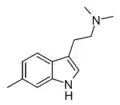

| 5-Methyl-DMT (5,N,N-TMT) | artificial | 5-CH3 | CH3 | CH3 | 5,N,N-trimethyltryptamine | 22120-39-4 |

| 6-Methyl-DMT | artificial | 6-CH3 | CH3 | CH3 | 6,N,N-trimethyltryptamine | |